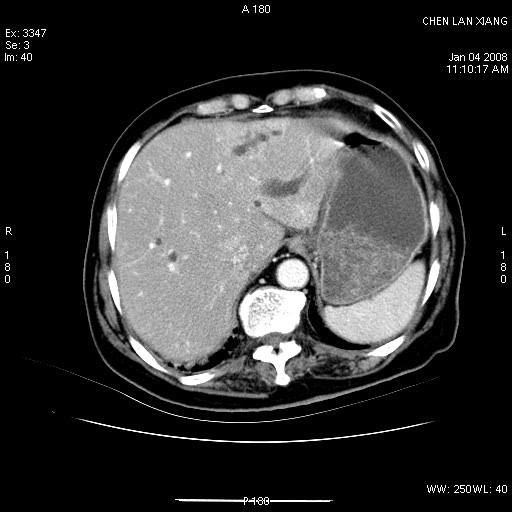

标题: CT11180:女,76岁,腹痛3-4天 [打印本页]

标题: CT11180:女,76岁,腹痛3-4天

女,76岁,腹痛3-4天,b超示:肝内实性肿物,胆囊强回声,胆总管扩张.

考虑:1、胆总管下端结石伴梗阻性肝内外胆管扩张(肝左叶外侧段肝内胆管多发结石、胆管炎);

2、肿囊癌累及肝,不除外 黄色肉芽肿性胆囊炎。

1 胆总管末端结石伴肝内胆管结石,肝内外胆管扩张。2 胆囊扩大,胆囊壁不规则增厚,内见软组织密度影。考虑:慢性胆囊炎,不除外胆囊癌!

标题: 肝右叶病灶

胆囊癌侵犯肝右叶?

1)胆囊癌伴肝脏转移。2)胆总管下端结石、肝内胆管结石伴肝内外胆管扩张。